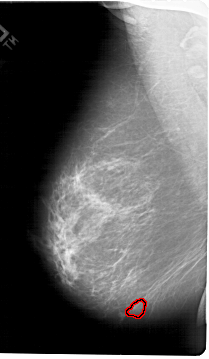

A_1789_1.LEFT_MLO

LEFT_MLO LINES 6811 PIXELS_PER_LINE 3961 BITS_PER_PIXEL 12 RESOLUTION 43.5 OVERLAY

FILE: A_1789_1.LEFT_MLO.OVERLAY

TOTAL_ABNORMALITIES 1

ABNORMALITY 1

LESION_TYPE MASS SHAPE LOBULATED MARGINS OBSCURED

ASSESSMENT 4

SUBTLETY 3

PATHOLOGY BENIGN

TOTAL_OUTLINES 1

BOUNDARY